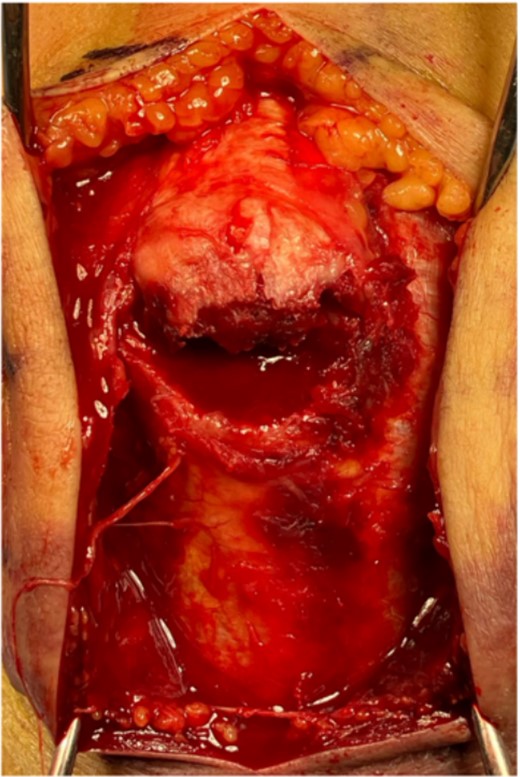

The surgery was performed in the left lateral recumbent position. An incision was made in the posterior midline over the right olecranon. Triceps brachii tendon rupture was not observed (Fig. 2). The fracture fragment was inverted, and two 1.4-mm JuggerKnot® All-Suture Anchors (Zimmer Biomet, USA) were inserted into the ulna proximal to the fracture site without perforation into the elbow joint. Subsequently, sutures were threaded through the triceps brachii muscle; the dislocated bone fragment was pulled together with the triceps brachii muscle. Despite maintaining the elbow at a 30° flexion position, two Quattro® Link Knotless anchors (Zimmer Biomet, USA) were inserted into the ulna distal to the fracture site to reduce and fix the fragment using the suture bridge procedure (Fig. 3). However, upon flexing the elbow joint to 90°, the bone fragment was displaced and anchors were loose. Therefore, we opted to use the McLaughlin cerclage technique, utilizing a 2.3-mm BroadBand® Tape (Zimmer Biomet, USA) passing through a predrilled hole perpendicular to the ulnar shaft. The suture was crossed over the posterior aspect of the ulna and tightened in a figure-of-eight manner through the triceps brachii tendon (Fig. 4). This procedure resulted in no dislocation of the fracture site, even when the elbow joint was flexed to 130°.

The bone fragment is displaced, and its continuity with the triceps tendon is preserved.